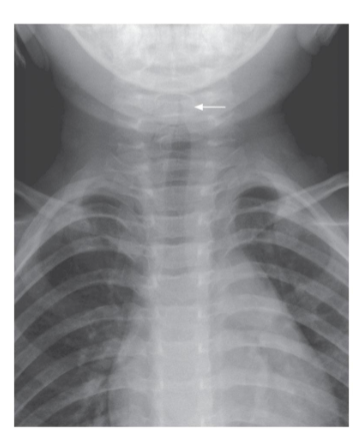

Croup

- Sign? Steeple sign.

- Diagnosis? Croup.